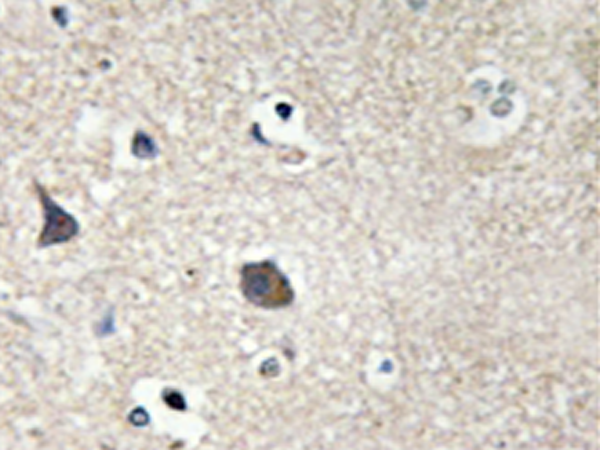

IHC positive control: |

Human brain tissue |

IHC Recommend dilution: |

50-100 |